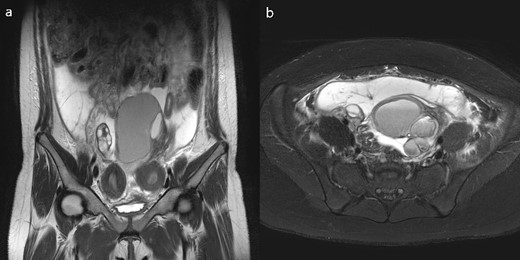

An 11-year-old girl who had menarche 14 months before visiting the emergency department in another hospital presented with abdominal pain and fever. She was transferred to our hospital after an abdominopelvic computed tomography revealed uterine anomaly, pelvic fluid collection, and left adnexal mass. Her primary dysmenorrhea was gradually worsening. Transabdominal ultrasonography showed a unicornuate uterus and noncommunicating functioning horn without hematocolpos. The 11-cm-sized low echoic left adnexal multiseptated cyst was observed, suggesting endometriosis, and the pelvic fluid collection was observed in the lower abdomen. She had a right single kidney and right unicornuate uterus with a left rudimentary horn, left adnexal cyst, and hemoperitoneum on pelvic cavity MRI (Fig. 2a and b), although she had never been diagnosed with a single kidney during prenatal scan. The left rudimentary horn does not communicate with the contralateral uterus or vagina, and the left vagina was not observed; thus, an obstructed Müllerian anomaly that does not correspond to typical OHVIRA syndrome was confirmed. As of ASRM Müllerian anomalies classification 2021, it corresponds to the right unicornuate uterus with left distal uterine remnant with functional endometrium. The fever could be caused by pyometra or pyosalpinx. Thus, empirical antibiotics were first given, and diagnostic laparoscopy was planned for surgical treatment to prevent recurrent hemoperitoneum. Hysteroscopy was performed to identify the disconnection between the right hemivagina and left hemiuterus. Hemoperitoneum was observed at the beginning of laparoscopy, and the operation was switched to laparotomy because of severe pelvic adhesion. The left noncommunicating rudimentary horn was excised after adhesiolysis, and the left adnexal cyst was removed from the normal ovarian tissue. Endometriosis was histologically confirmed at the left adnexal cyst specimen. Ultrasonographic follow-up was performed 1 month and 6 months postoperatively. No recurrence of endometriosis and no other abnormalities were observed for 3 years postoperatively.

(a) T2 coronal view, (b)T2 axial view of pelvic cavity MRI of Case 2; MRI revealed a unicornuate uterus with a non-communicating rudimentary horn and unilateral ovarian endometriosis and hemoperitoneum.